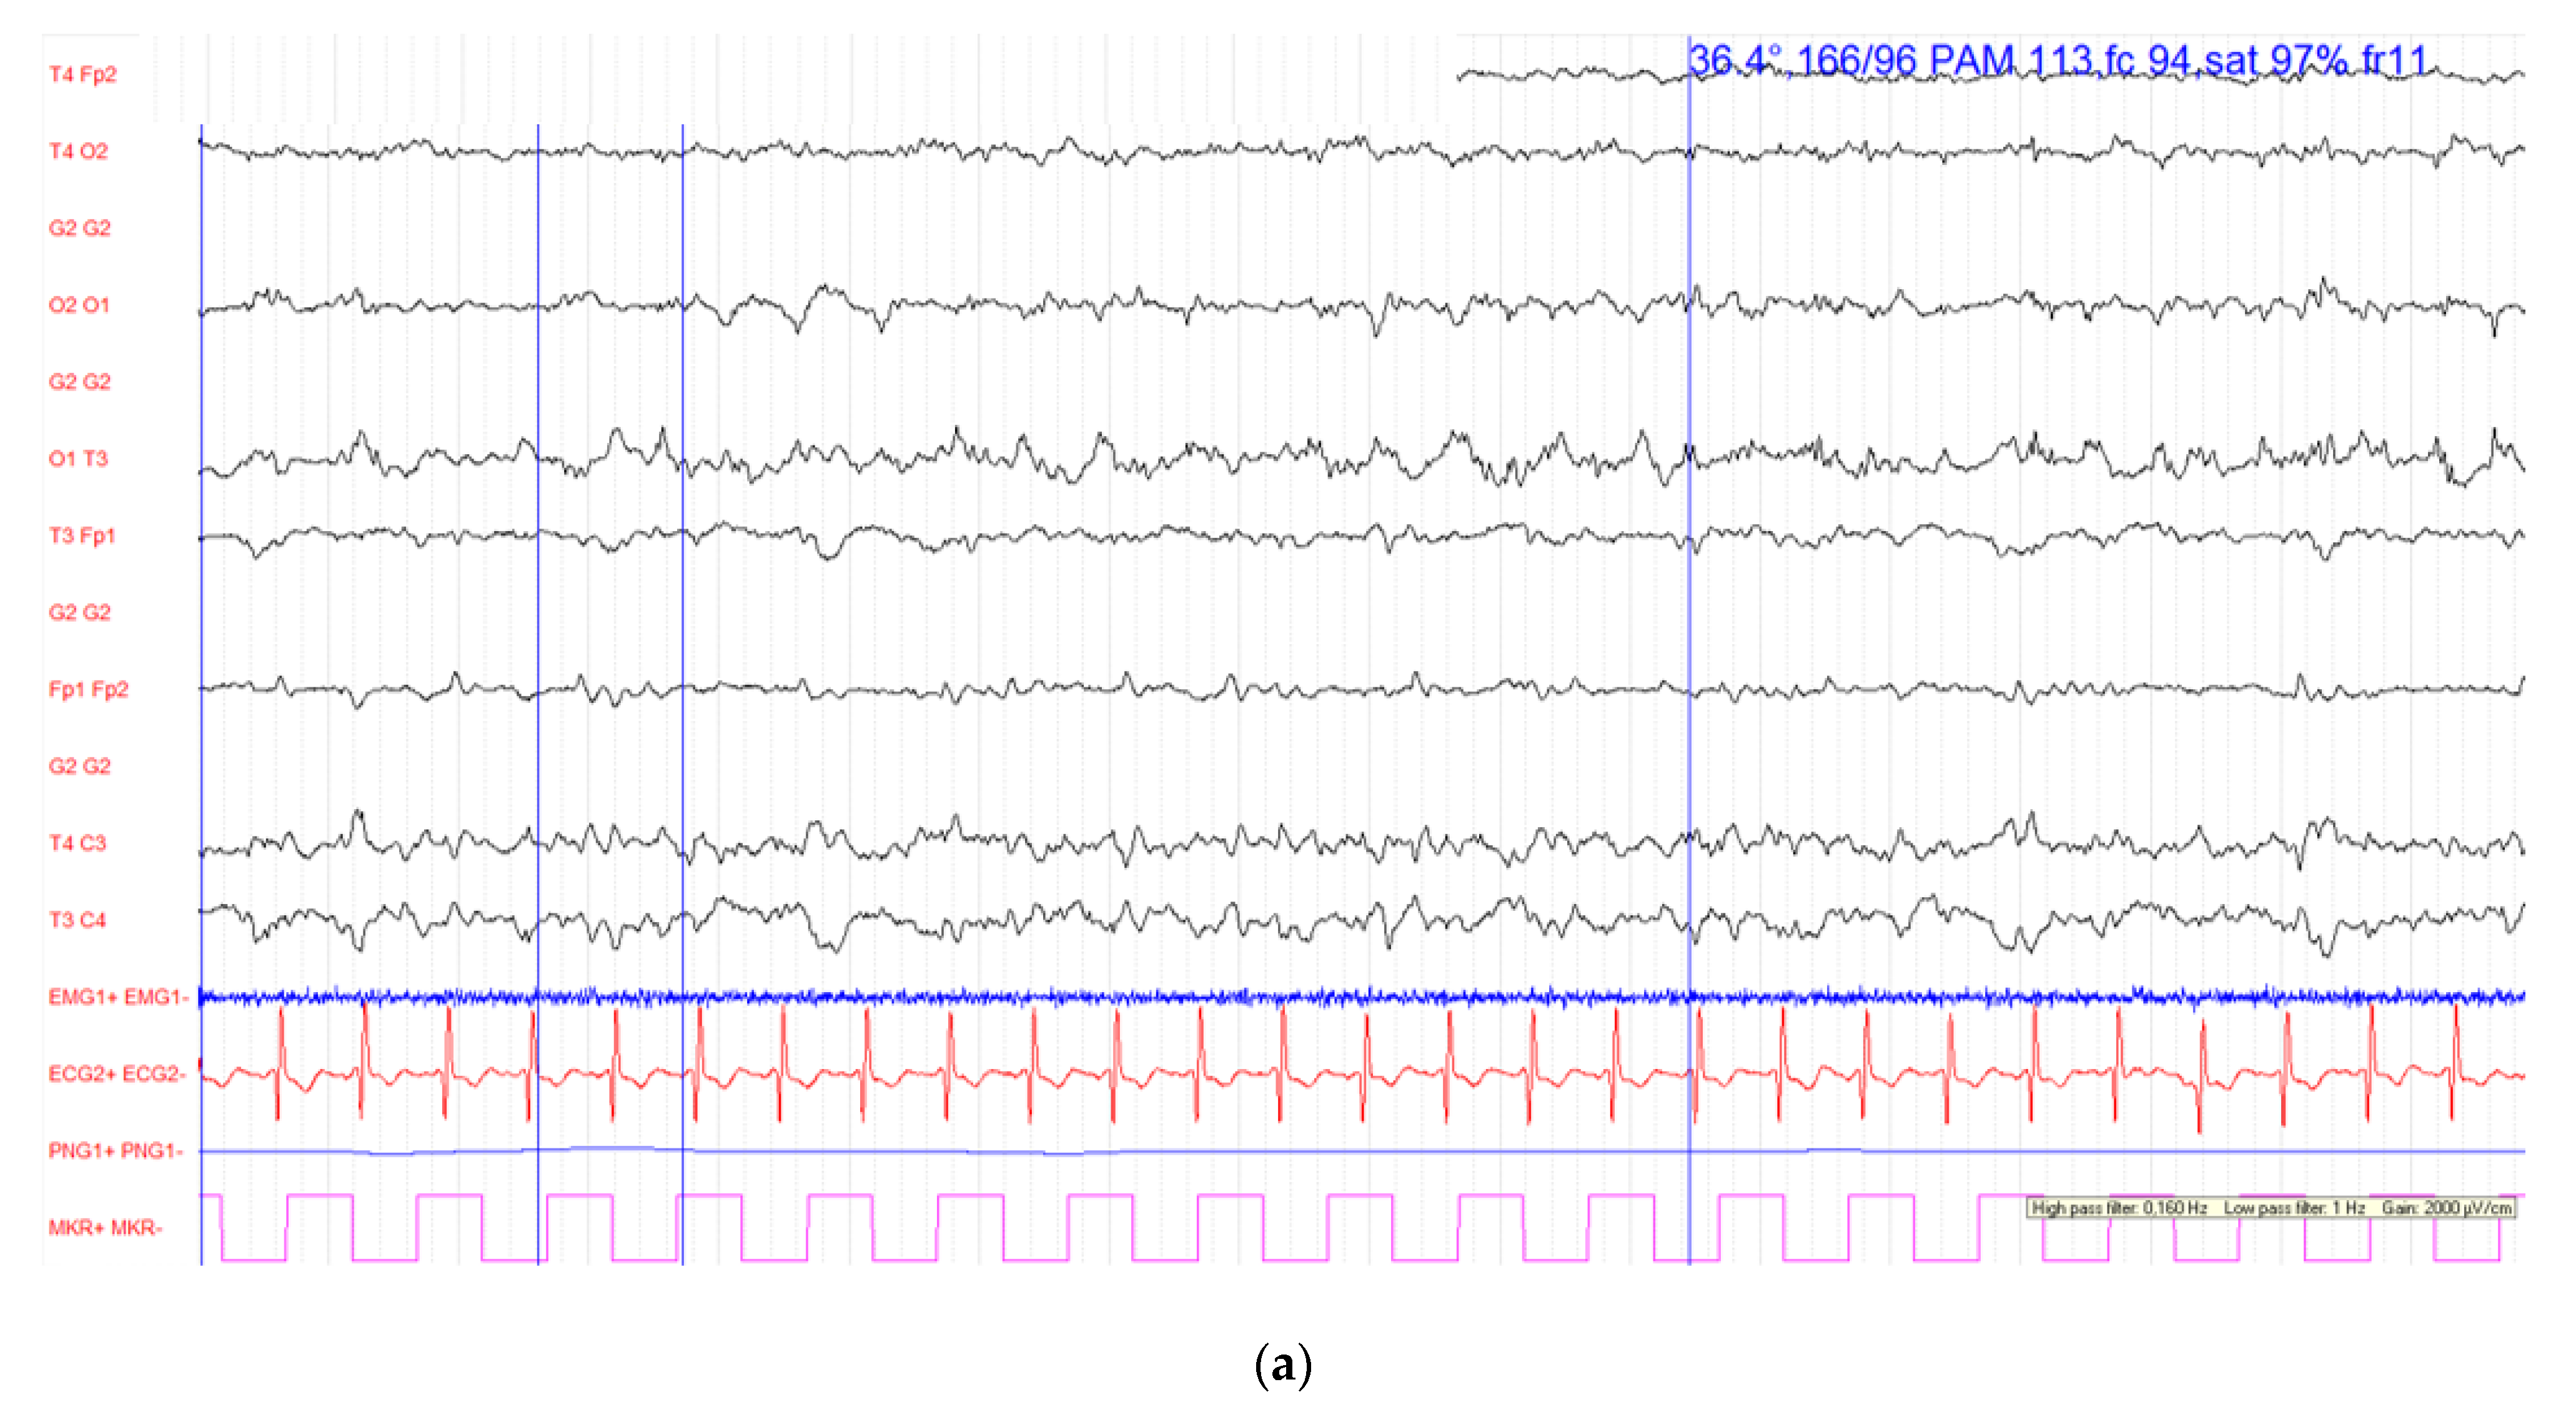

The first cycle of carboplatin (area under the curve (AUC) of 5) and etoposide (100 mg/m2 daily on days 1–3) with a combination of an ICI (atezolizumab at a dose of 1200 mg on day 1) was delivered without immediate side effects. Nevertheless, the following day the patient presented consciousness disorders (a Glasgow score of 5/15) associated with a partial epileptic seizure (tonic-clonic seizure of the right upper limb), that was secondarily generalized. The partial epileptic seizure persisted despite optimal management with the administration of clonazepam and levetiracetam. Therefore, the patient was transferred to the intensive care unit (ICU) where he received phenytoin and corticosteroids. His arterial blood pressure was elevated (206/108 mmHg), with increased heart and respiratory rate but without fever. On neurological examination, he demonstrated a right hemiplegia, a facial paralysis of the right hemiface and a right pyramidal syndrome. Glycemia was normal. The electroencephalograms performed on the first and second day of the symptoms are shown in Figure 1.

Figure 1.

Electroencephalograms (EEG) performed on the first and the second day of symptoms. All channels from R1020 montage are present. EEG configurations are: high pass filter = 0.53 Hz; low pass filter = 70 Hz; scaling = 100 μV/cm. (a) First day: Lesional left occipital status epilepticus (b) Second day: the background activity appears asymmetrical with a slowed rhythm in the left hemisphere. There are theta delta activities of sometimes periodic expression focused on the left centro-parietal region. Absence of seizure.

The initial brain computed tomography (CT), pre- and post-contrast administration, was performed on a SOMATOM Force (Siemens Healthineers, Forchheim, Germany) CT scanner at 12 mAs and 3 kV. Images were reconstructed with filtered back projection (FBP) and the advanced modeled iterative reconstruction (ADMIRE; Siemens Healthineers). It showed no evidence of stroke, bleeding or brain metastasis. The Circle of Willis was permeable with the detection of an atheromatous infiltration of the carotid bulbs with a loose stenosis. The electroencephalogram showed a left occipital status epilepticus.